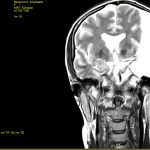

Für diejenigen von Euch, die es auch immer wieder mal interessiert wie es in meinem Kopf aussieht, habe ich hier zum einen mal drei der vielen Bilder von gestern

Außerdem gibt es die Möglichkeit mal eine kurze „Durchreise“ durch meinen Kopf zu machen. Dafür habe ich Euch hier mal zwei Screeningsfrequenzen von gestern hochgeladen. Einmal Frontal und einmal seitlich. Bei der Frontalsequenz ist es so als ob ihr quasi von vorne durch mein Gesicht nach hinten durchschaut. Deshalb ist mein Untermieter somit auf der rechten Seite in den Aufnahmen zu sehen (eigentlich nicht zu übersehen so groß und in dem Fall schwarz er auf den Aufnahmen ist). Bei der Seitensequenz schaut ihr quasi von der linken Seite meines Kopfes hindurch bis zur rechten. Sozusagen so, als ob ihr mir von meiner linken Schulter kommend hindurch bis zur rechten Schulter durchläuft. Da die Aufnahmen von der linken Seite her kommend sind läuft ihr quasi direkt im Untermieter beginnend los und deshalb habt ihr da erst mal dann in voller Größe eine schwarze Fläche an Untermieter bevor die ungefähr Höhe Nase in einen „normalen Bereich“ wo dann im kompletten Schädel Hirnmasse zu sehen ist – meiner rechten Hirnhälfte – durchläuft.

Tja das sind nun wenige Teile der gestern neu gemachten Aufnahmen. Ich denke unschwer zu erkennen, dass mein Untermieter sich nach wie vor in voller Pracht präsentiert. Auch der Doc meinte gestern so, dass es immer wieder erstaunlich wäre. Er selbst hätte in seiner ganzen Karriere noch nie einen Untermieter solchen Ausmaßes gesehen. Ich bin mir sicher, der wird mich in seinem ganzen Leben nie vergessen. ![]()